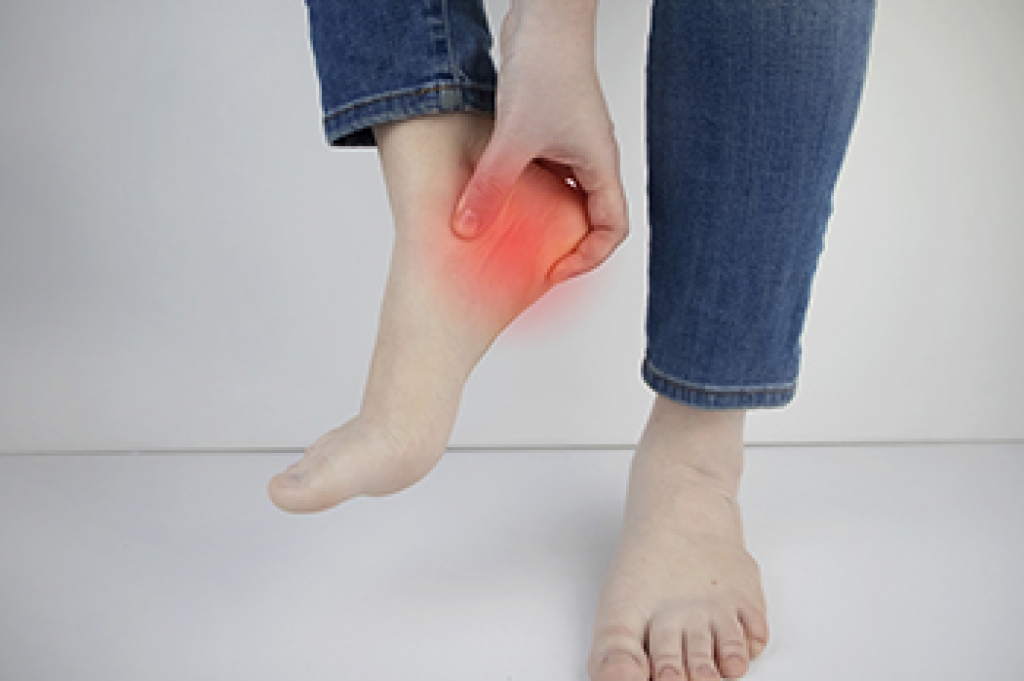

Heel pain is often caused by excessive pressure, injury, or strain. The heel’s fatty cushion helps absorb impact during movement, but activities like running, jumping, or standing on hard surfaces can lead to pain. This is particularly true among older adults, pregnant women, and people who are overweight. Ill-fitting shoes and abnormal walking patterns can also contribute to heel pain. Plantar fasciitis, a common cause, occurs when the band of tissue along the sole becomes inflamed, often resulting in sharp pain under the heel. Heel spurs, which are bony growths on the heel bone, can develop from chronic strain and can be painful. In children, Sever’s disease is a frequent cause of heel pain due to stress on the heel bone's growth plate during physical activity. A podiatrist can evaluate your symptoms, identify the root cause, and provide effective treatment, including custom orthotics, supportive footwear, or other measures to alleviate pain and improve foot function. If you are experiencing heel pain, it is suggested that you schedule an appointment with a podiatrist to find out the cause, and receive the appropriate treatment.

Heel pain is often associated with plantar fasciitis. The plantar fascia is a band of tissues that extends along the bottom of the foot. A rip or tear in this ligament can cause inflammation of the tissue.

Achilles tendonitis is another cause of heel pain. Inflammation of the Achilles tendon will cause pain from fractures and muscle tearing. Lack of flexibility is also another symptom.

Heel spurs are another cause of pain. When the tissues of the plantar fascia undergo a great deal of stress, it can lead to ligament separation from the heel bone, causing heel spurs.

Heel pain should be treated as soon as possible for immediate results. Keeping your feet in a stress-free environment will help. If you suffer from Achilles tendonitis or plantar fasciitis, applying ice will reduce the swelling. Stretching before an exercise like running will help the muscles. Using all these tips will help make heel pain a condition of the past.